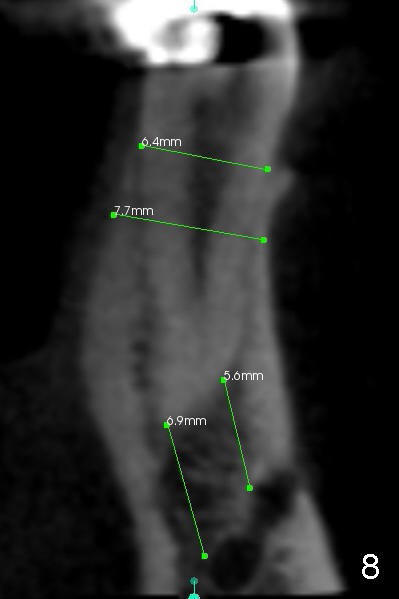

下颌第二前磨牙CT矢状切面显示近远中宽四毫米(图六),冠状切面显示颊(图七B)舌(L)侧宽约六毫米(图八),颏神经襻(*)颊侧比舌侧高,如果即刻植牙偏向舌侧(图九红色),颏神经受损可能性减少。如果即刻植牙局限于拔牙窝(图九虚线),那么更安全(1 2)。